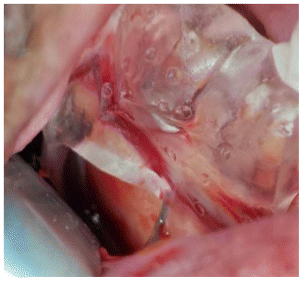

- The harvest guide was then placed, and the FGG harvest was performed. (Figure 11,12)

- The donor site was packed with a hemostaticcollagen sponge from Gelitaspon (GELITAMEDICAL GmbH, Eberbach, Germany).

- Graft was then de-epithelialized extra orally.

- Graft was placed submarginally and sutured to theflap. (Figure 13).